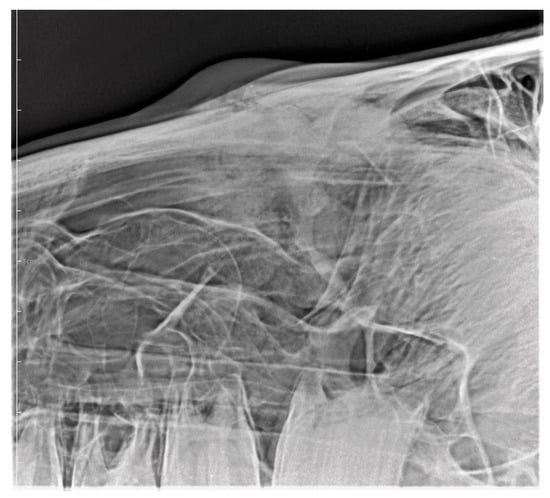

3.2. Imaging Findings